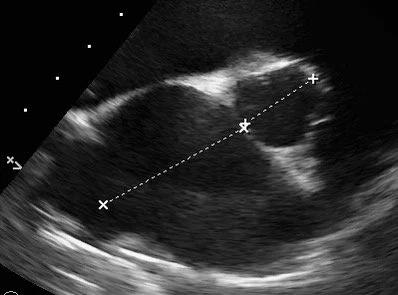

Echocardiography scan of dog's heart